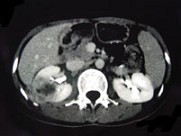

- 多项选择题女,33岁, 右胁腹痛7天,尿检可见大量的脓细胞, CT平扫+增强如图所示,下列说法正确的是 ( )

A、右肾体积增大,其内可见类圆形低密度病灶

B、增强扫描可见该病灶不均匀强化,其内有无强化的坏死灶

C、右肾病灶边界模糊不清

D、考虑为右肾囊肿合并感染

E、考虑为右肾脓肿